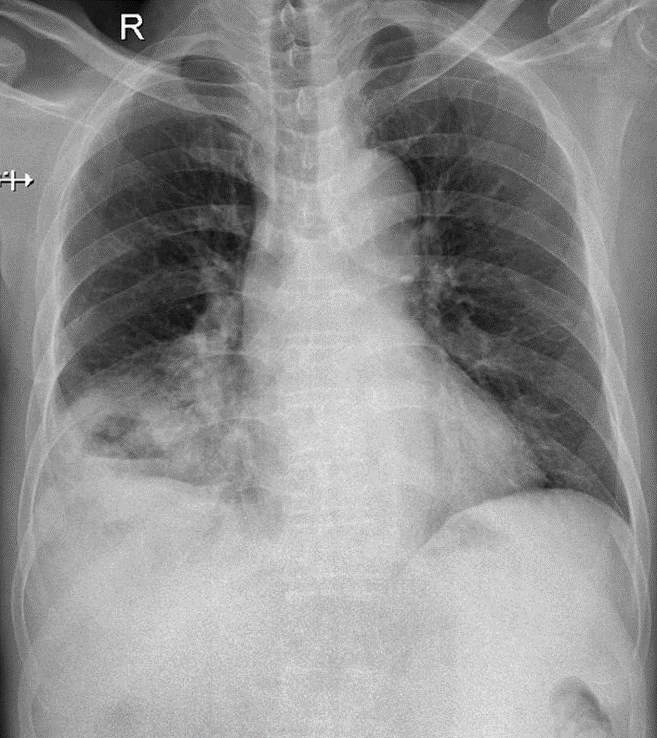

Hãy phân tích tình huống Nữ 54 tuổi -CĐ:Tràn dịch màng phổi (P) lượng nhiều nghi do lao

1-Khí quản lệch (T) 2-Tràn dịch màng phổi (P) lượng nhiều 3-Bóng tim và trung thất lệch (T)